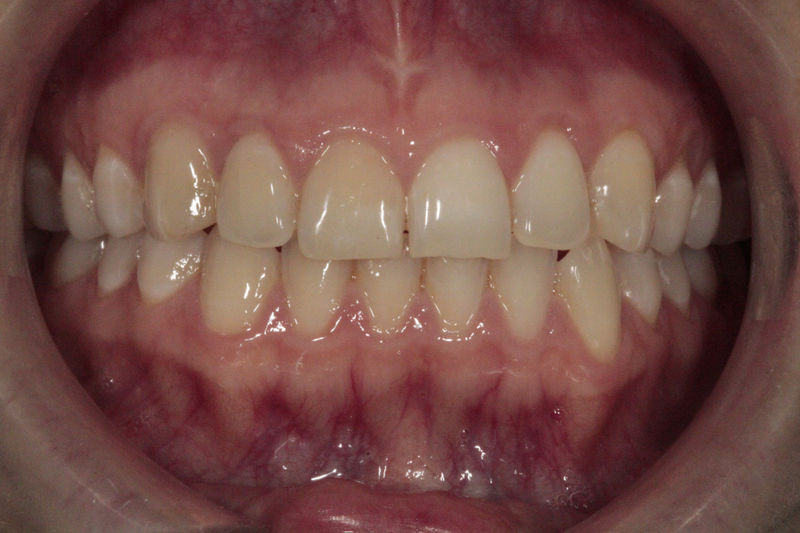

Implantes, ortodoncia y coronas.